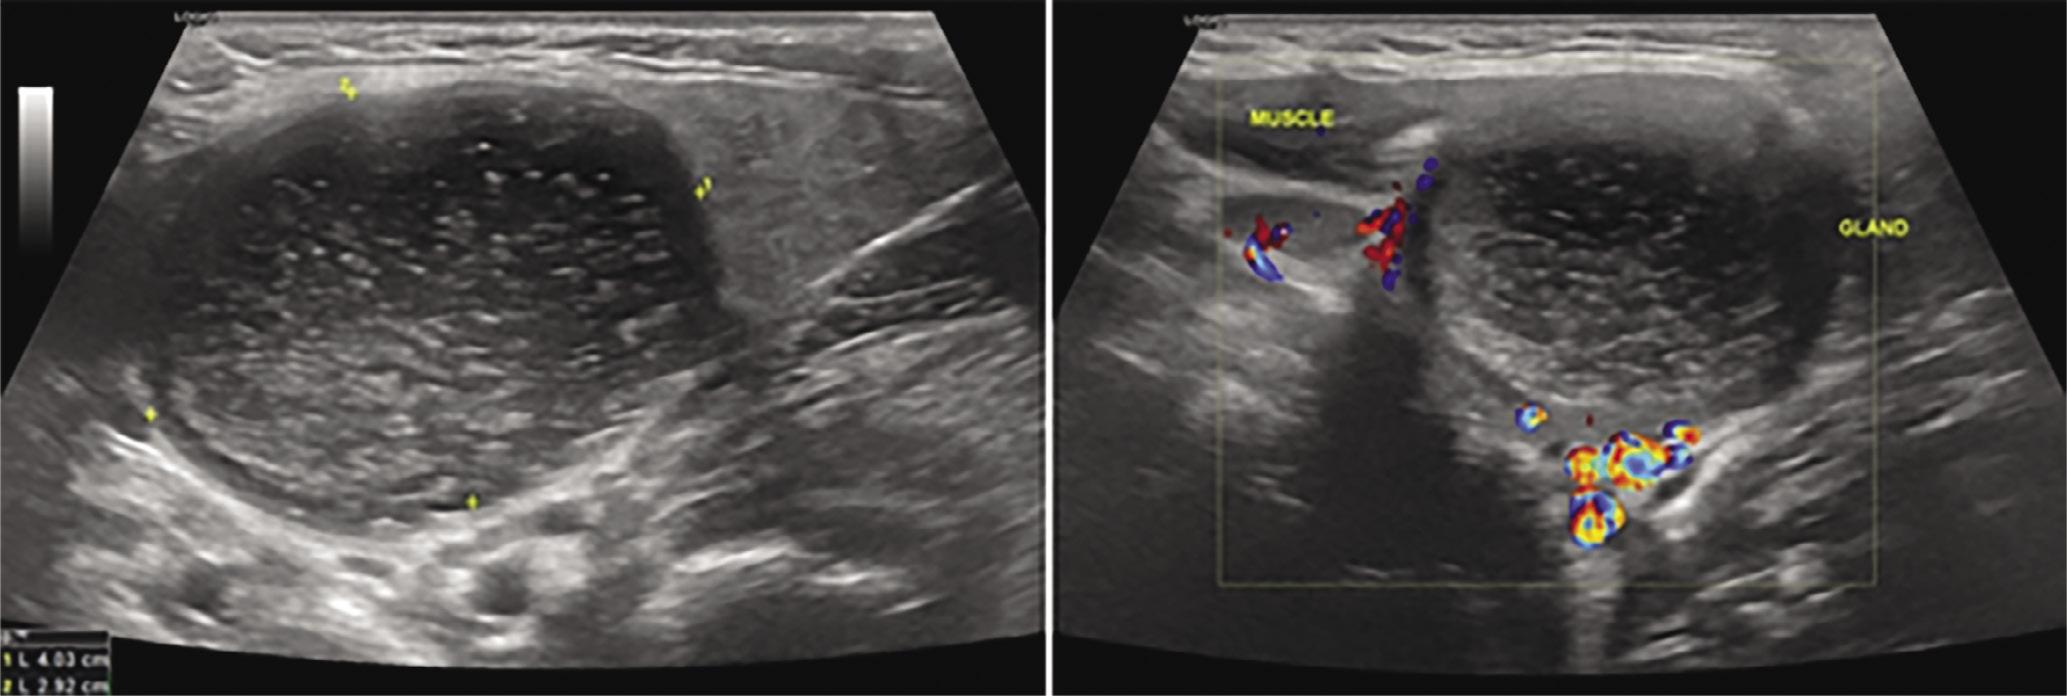

| 1st cleft | 9 | 5/4 | All hypoechoic | 2/7 |